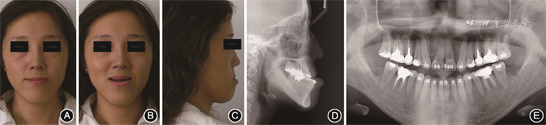

(1)术前正畸治疗:拔除22、18、28、38、48,粘接全口直丝弓矫治器,采用直丝弓矫治技术。上颌初始弓丝为0.356 mm(0.014英寸)镍钛圆丝,下颌初始弓丝为0.305 mm(0.012英寸)镍钛圆丝,依次更换0.356 mm(0.014英寸)、0.406 mm(0.016英寸)镍钛圆丝,0.406 mm×0.559 mm(0.016英寸×0.022英寸)镍钛方丝,0.406 mm×0.559 mm(0.016英寸×0.022英寸)不锈钢方丝。矫治4个月后初步排齐上下牙列。矫治5个月后阶段模型示上下牙弓基本匹配;利用减数间隙调整上牙列中线,内收上前牙,33—43邻面去釉为下前牙排齐提供间隙。矫治8个月时取阶段模型:上下牙弓匹配,前牙反覆盖增大,继续关闭拔牙间隙,解除下前牙拥挤(图2,3)。矫治15个月时上下颌以0.406 mm×0.559 mm(0.016英寸×0.022英寸)不锈钢弓丝作为稳定弓丝,于相邻牙托槽间焊接牵引钩为正颌手术做准备,取模型制作终末

成年患者正畸治疗8个月时面像和影像学资料 A:正面像;B:正面微笑像;C:侧面像;D:头颅侧位X线片;E:曲面体层X线片

成年患者正畸治疗8个月时口内像 A:右侧

像;B:正面

像;C:左侧

像